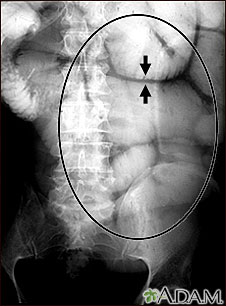

Esta radiografía abdominal muestra el engrosamiento de la pared intestinal y la hinchazón (distensión) provocados por una obstrucción intestinal. El paciente fue sometido a un procedimiento que se conoce como serie GI superior, para el cual ingirió un medio de contraste (bario) que es visible en los rayos X.